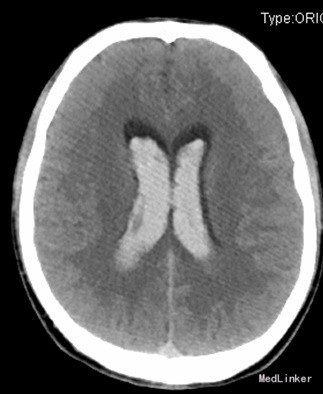

查体:昏迷,双瞳大形圆约3mm,四肢及肌力张力不合作。辅助检查:CT提示蛛网膜下腔出血,脑室铸型。头部CTA提示:广泛蛛血,脑室系统明显积血,脑实质稍肿,中线居中;右侧颞叶约侧脑室区积血内见增多、迂曲团状血管影,似主要由右大脑后动脉分支供血,考虑血管畸形可能性大。行全脑血管造影提示右侧小脑动静脉畸形,供血动脉来自右侧小脑上动脉、右侧大脑后动脉。